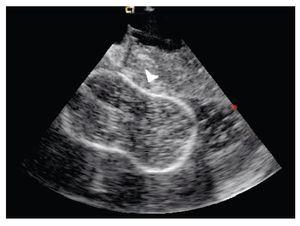

The transeptal puncture was performed under direct ultrasound guidance (Figure 1). After hemodynamic confirmation of left atrial curve morphology, the Mullins catheter was advanced and exchanged for a spiral guide-wire. Interatrial septum was dilated with the usual technique and an Inoue 28 balloon was advanced through the mitral valve into the left ventricle under direct ultrasound guidance (Figure 2). Mitral valvuloplasty at the level of the valve (Figure 3) was performed by a single inflation with the Inoue balloon with 28 ml of normal saline. ICE analysis across the mitral valve showed a significant drop of mean transmitral valve gradient and an increase of the mitral valve area, without an increase of mitral regurgitation.

Figure 3. Shows the Inoue balloon inflated (arrow) with a waist in its middle; mitral valvular plane in long-axis view.